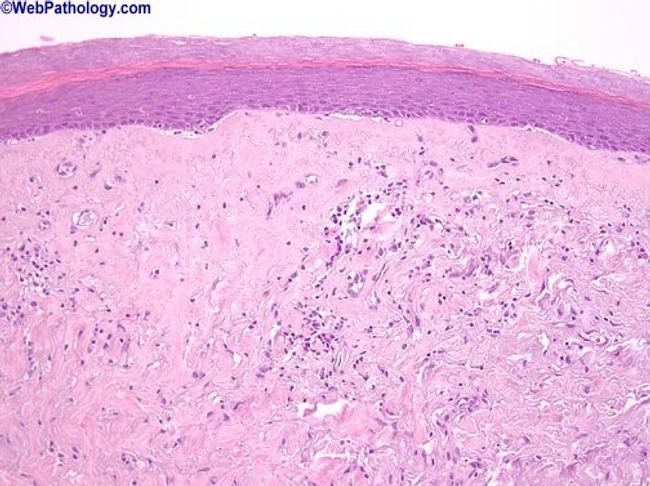

клероатрофический Лишай Фото